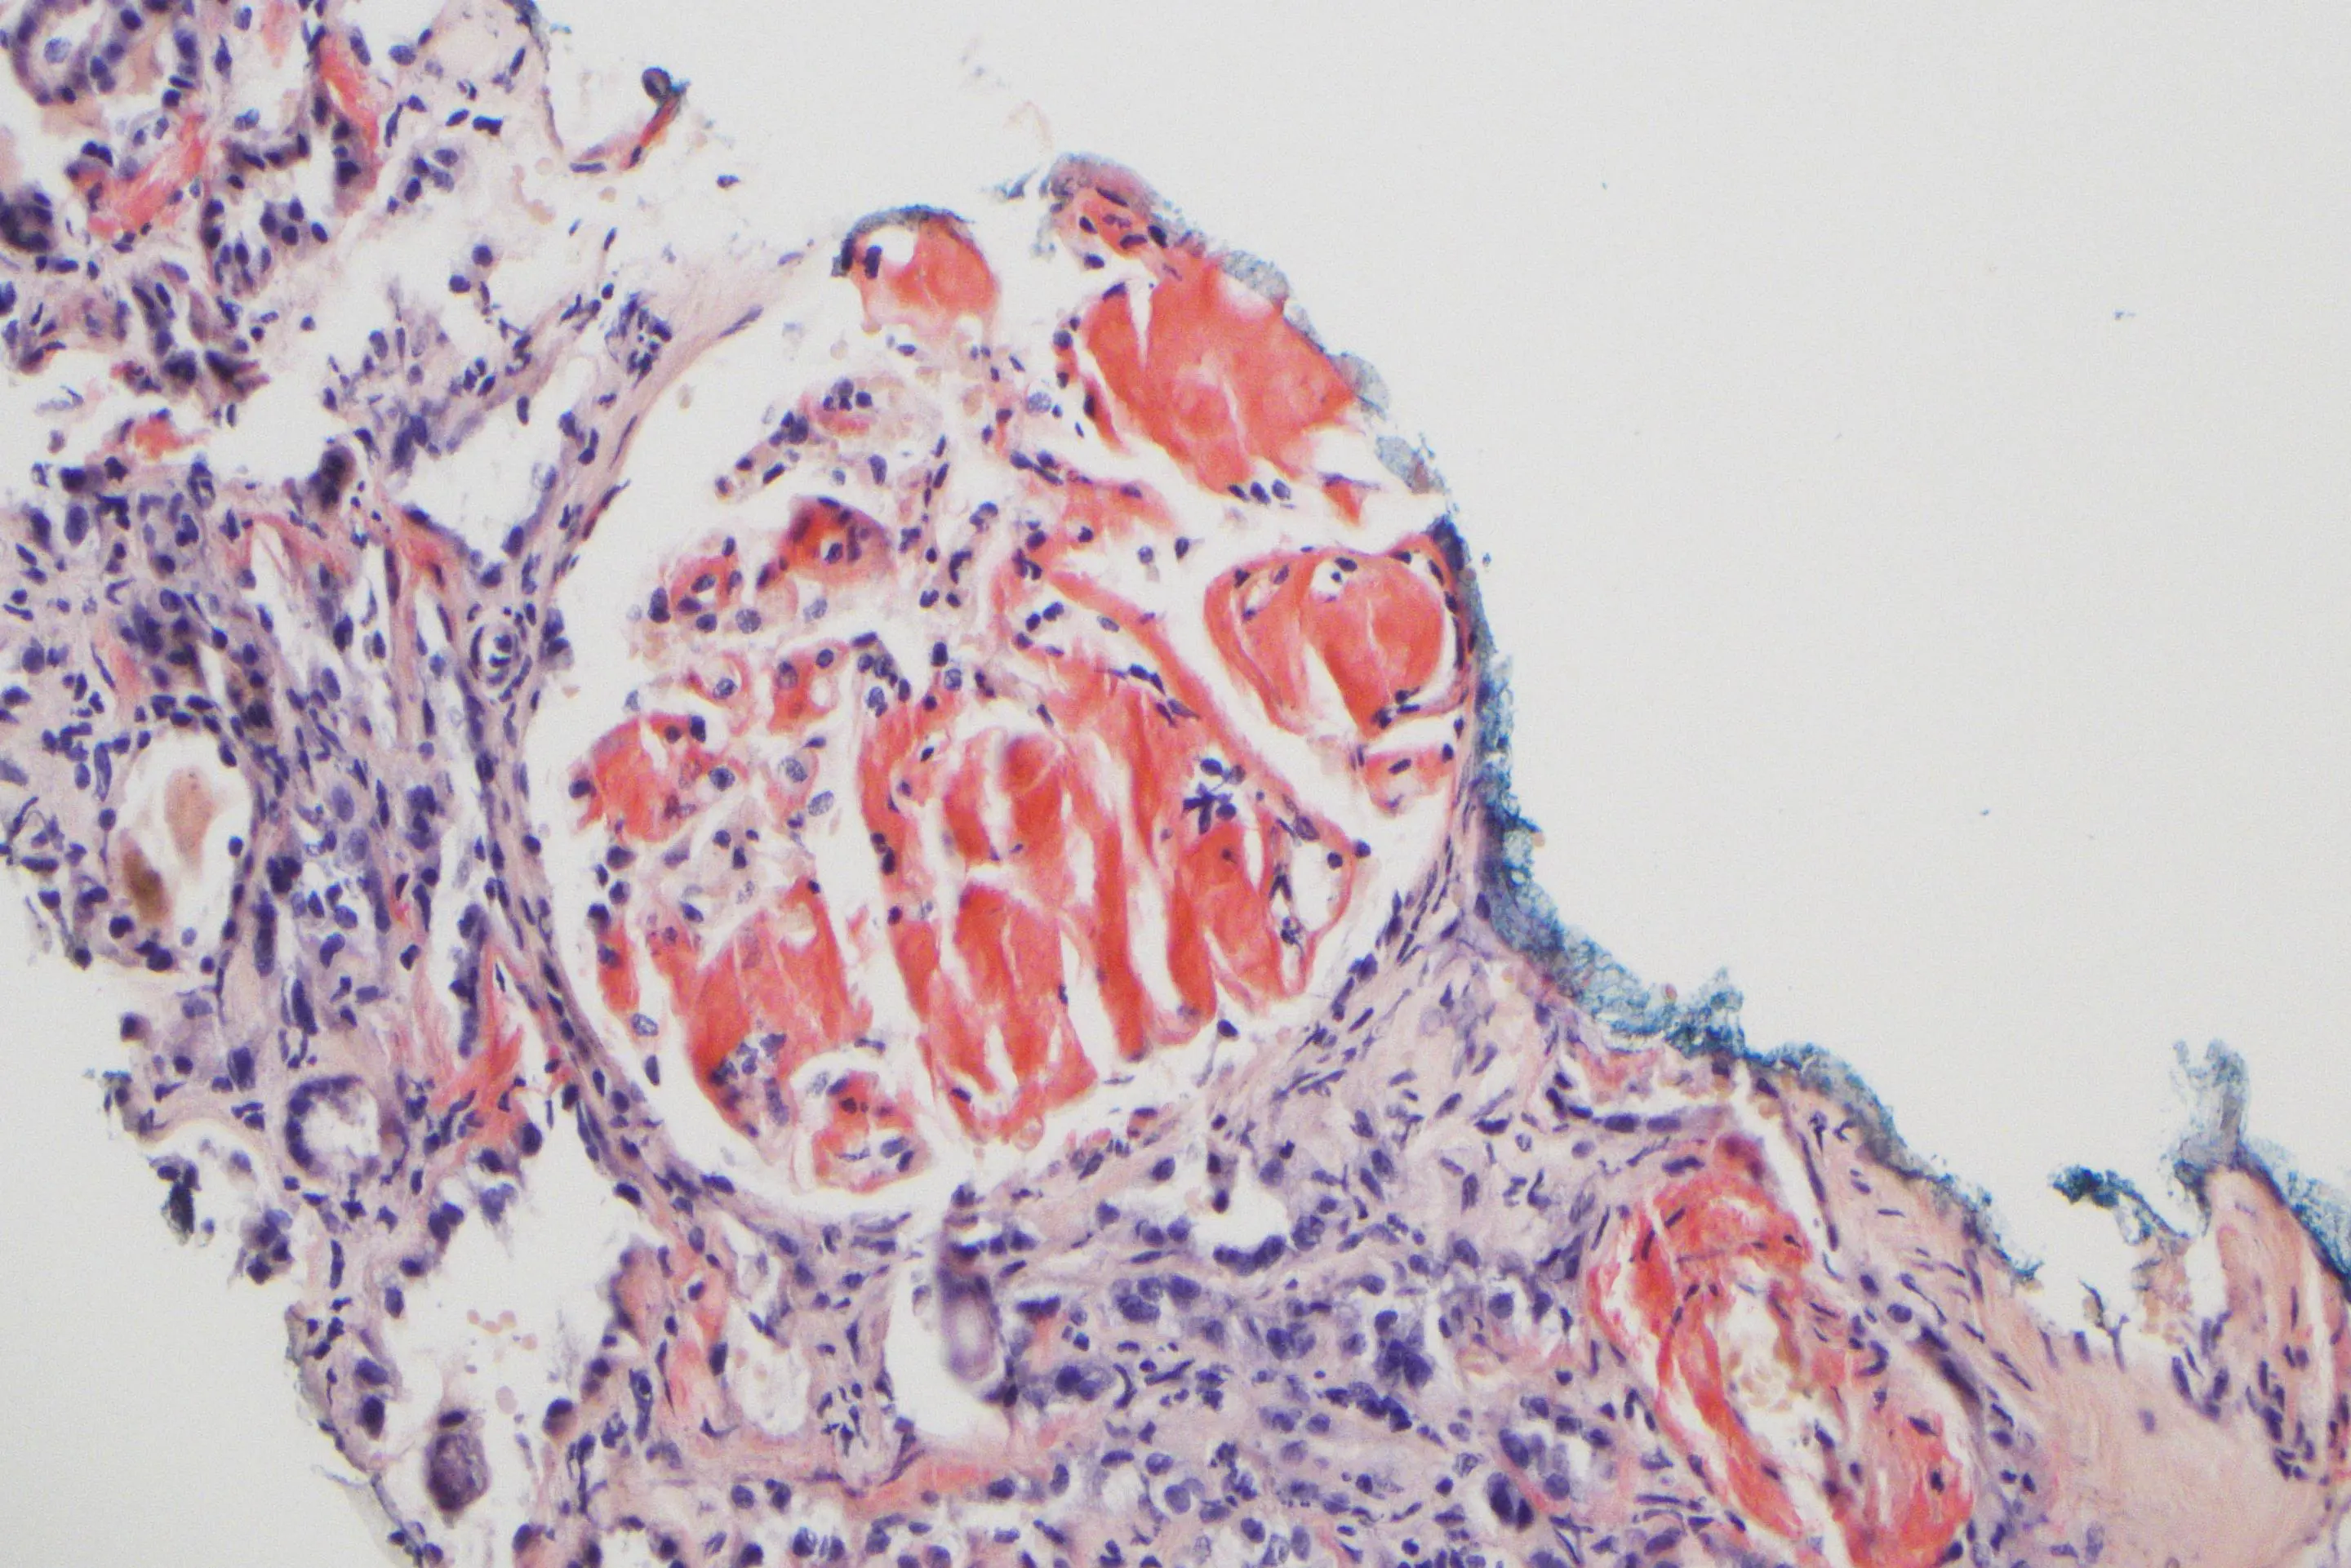

Amyloidose påvises ved å spesialfarge vevsprøve med et fargestoff som bindes til det avleirede proteinmaterialet (amyloid). Deretter må man undersøke hvilket protein som er avleiret. Dette er nødvendig fordi de ulike typene amyloidose krever helt ulik behandling.

AMYLOID. Vevsprøve fra nyre med amyloid spesialfarget med kongorødt. De rosa/røde feltene er avleiret amyloid i nyren. (Foto: Melinda Raki, avdeling for patologi, OUS)

Patolog i gruppen, Melinda Raki ved avdeling for patologi på Oslo universitetssykehus, forteller at avdelingen nå tar imot vevsprøver med amyloid fra hele landet. Prøvene blir undersøkt med immunhistokjemi og ved behov gjøres også spesialundersøkelser med ny teknologi (lasermikrodisseksjon med påfølgende proteomisk typing).